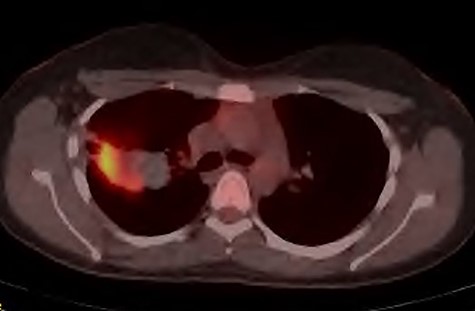

Initial investigations included a full blood panel with inflammatory markers (all within normal range) and a plain chest radiograph which demonstrated a mass in the right upper zone (Fig. 1). Computer tomography pulmonary angiogram (CTPA) scan demonstrated an 8 x 6.5 cm soft-tissue lesion within the right upper lobe (Fig. 2). This mass appeared to extend from the right hilum to the pleural surface and contained multiple small arterial branches. Her delivery date was brought forward pending further investigations. Positron emission tomography CT (PET-CT) demonstrated this lesion to be intensely fluorodeoxyglucose (FDG) avid (Fig. 3).

PET-CT demonstrating the right upper lobe lesion to be intensely FDG avid.